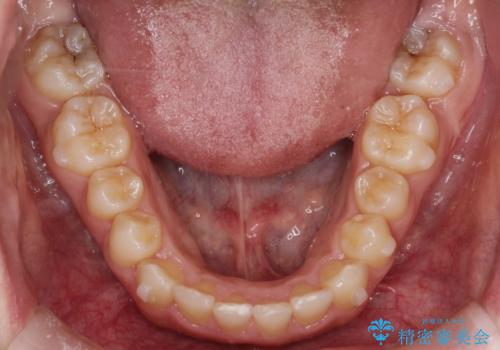

初診時の歯並びの状態としては、上下ともに全体に及ぶの中等度以上のがたつき(叢生)があり、全額的に歯列のアーチが内側に押しつぶされた状態でした。

強い叢生がありましたが、抜歯は行わず上下顎ともに、主に歯列弓の拡大を行い叢生を改善しました。